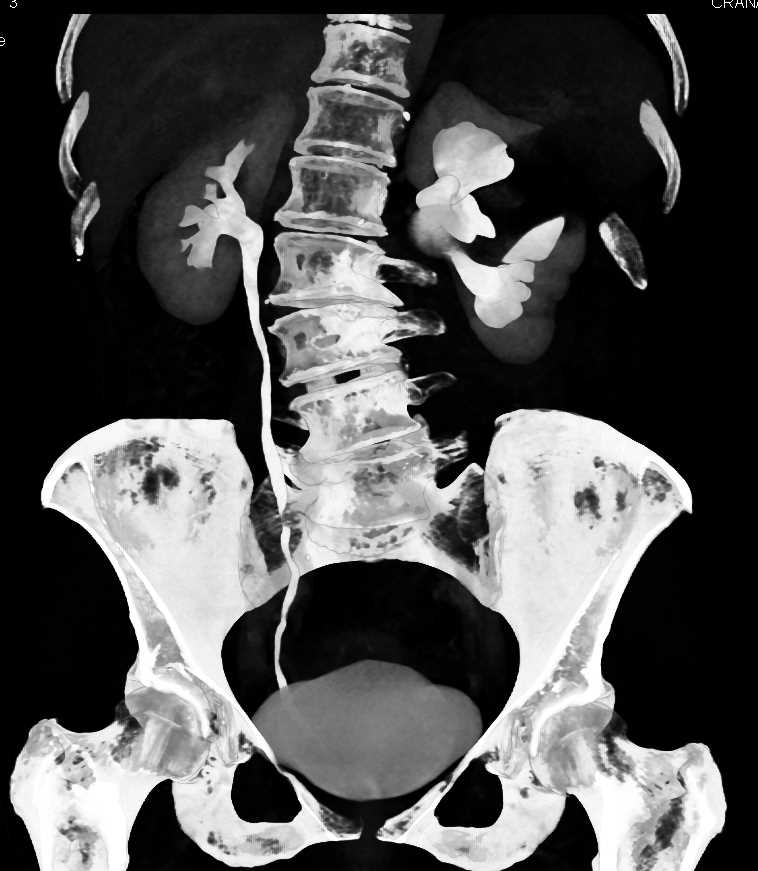

Parapelvic Cysts Left Kidney